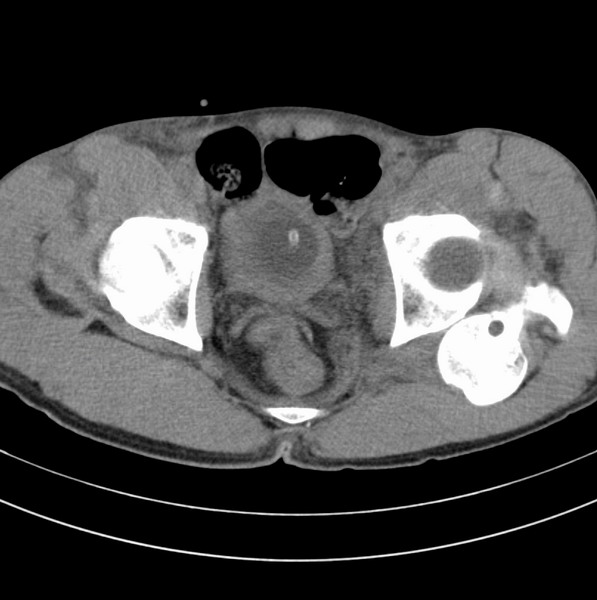

标题: CT18589:股骨头囊状阴影怎么下结论?

男、53

股骨头内的囊状阴影怎么下结论?

1.左髋后脱位。

2.囊状影考虑退变。

髋关节脱位、股骨头疝窝。

左髋关节脱位,其内圆形低密度影,考虑为股骨头疝窝

左侧髋关节后脱位;左侧股骨头疝窝。

左侧髋关节后脱位;左侧股骨头疝窝

脱位够厉害的